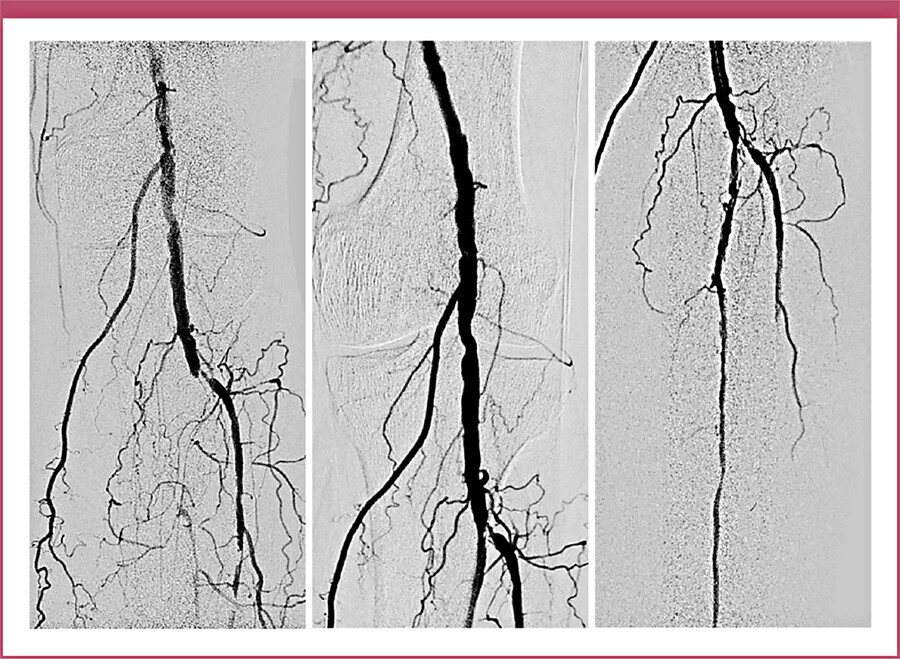

Therapie – es wird blutig

Bei Vorliegen eines DFS mit PAVK muss die Indikation für Revaskularisierungsverfahren (endoluminale und/oder gefäßchirurgische Eingriffe) frühzeitig und aggressiv erfolgen. Oftmals erfolgt die Überlegung erst dann, wenn die Fußläsion über Wochen nicht heilt oder die Indikation zur Amputation besteht. Ohne ausreichende Durchblutung ist aber eine Wundheilung nicht zu bewirken. Endovaskuläre Behandlungen mit Ballondilatationen, Stenting, Athe-rektomien aller Gefäßsegmente und gefäßchirurgische Optionen, z.B. crurale Bypassanlagen, stehen flächendeckend zur Verfügung. Durch stetig verbesserte Materialien und Verfahren sind alle Gefäßprovinzen zu erreichen und mit sehr guten Offenheitsraten zu behandeln.

Herr M. konnte nach u.a. endovaskulärer Versorgung mit einer Amputation des 4. und 5. Strahls des linken Fußes inkl. Mittelfußknochen-Resektion, Vakuumtherapie (VAC-Therapie), gefolgt von fünfmonatiger Wundbehandlung im ambulanten Setting behandelt werden. Der Unterschenkel ist ihm geblieben.